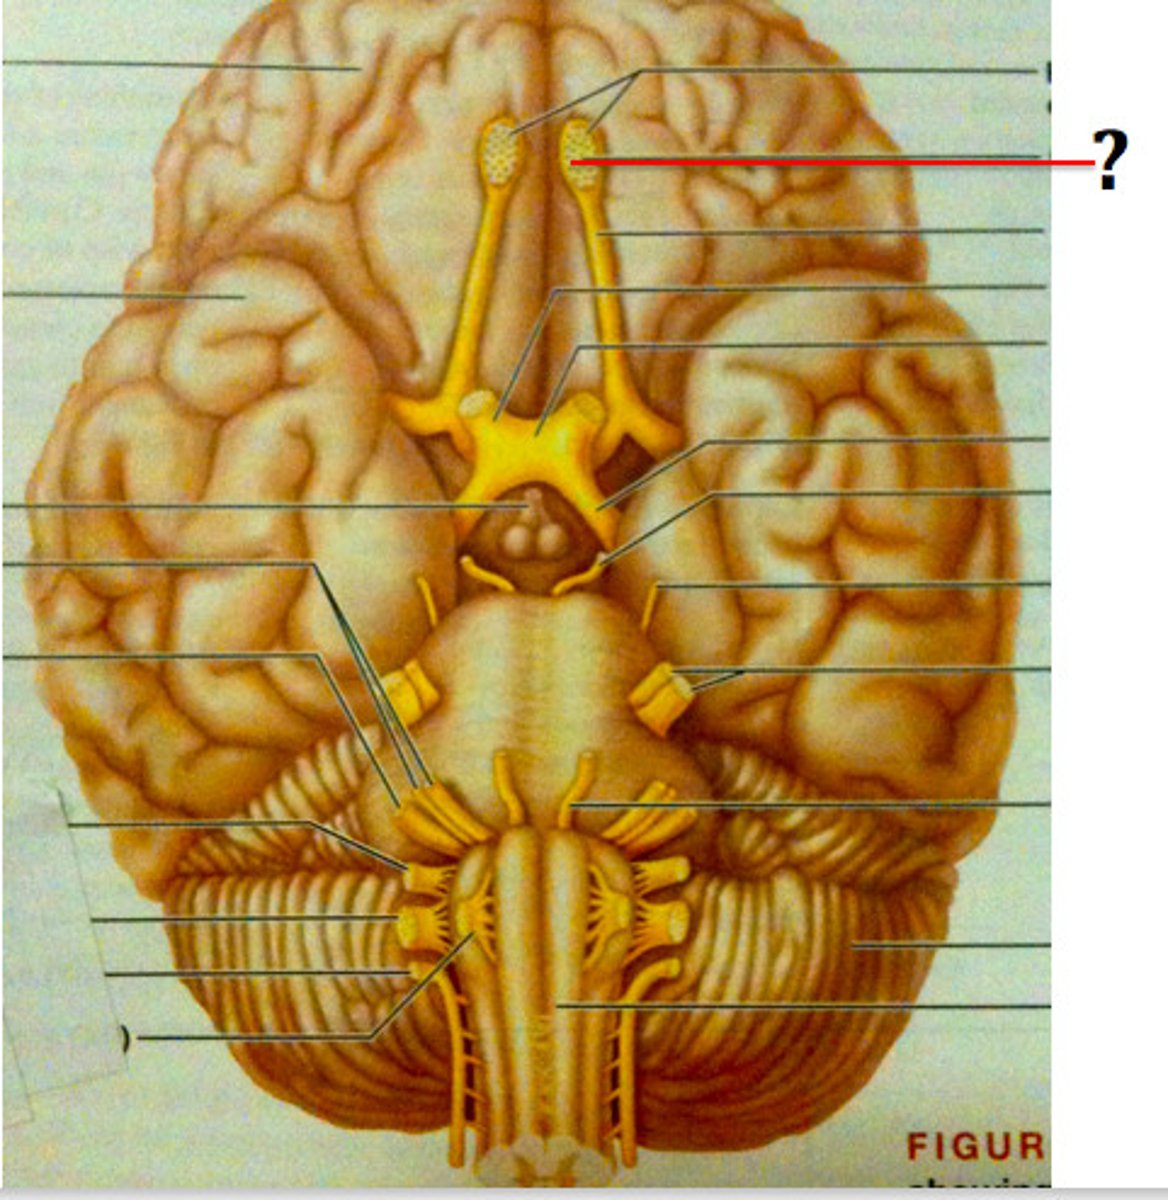

cranial nerves

12 pairs of nerves that carry messages to and from the brain

olfactory bulbs

rests on the cribriform plate. related to smell (olfaction)